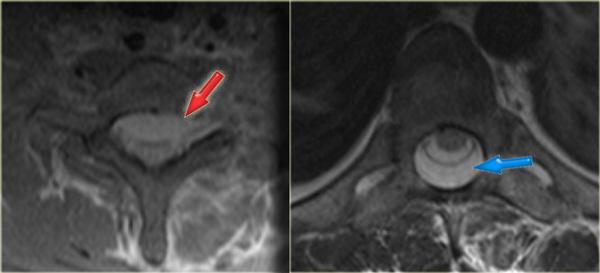

Hình ảnh bên trái thể hiện tổn thương tủy sống sau vết thương đâm bằng tua vít.

Trường hợp này dẫn đến hội chứng Brown-Séquard do cắt ngang nửa tủy sống.

Hội chứng Brown-Séquard

- Yếu vận động cùng bên và mất cảm giác đối bên do cắt ngang nửa tủy sống.

- Hội chứng Brown-Séquard có thể do chấn thương xoay như gãy-trật khớp hoặc chấn thương xuyên thấu như vết thương đâm.